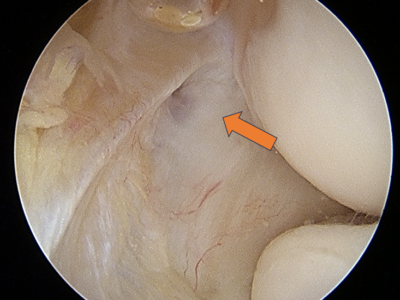

Minimally Invasive Arthroscopy – Small incisions (less than 1cm) for faster recovery and minimal scarring

Common Procedures – Tendon repair (for tennis/golfer's elbow). arthroscopic debridement (for arthritis). fracture fixation. ligament reconstruction (Tommy John surgery). etc.